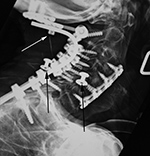

| Gown snaps simulating cervical spine apparatus |

| 70 year-old woman with severe rheumatoid arthritis and chronic atlantoaxial subluxation. There is occiput to T1 posterior spinal fusion and anterior spinal fusion from C3 to C7. One of the occipital screws is "proud" (white arrow). Two gown snaps (black arrows) simulate dislodged apparatus. A tracheostomy tube is also present. |